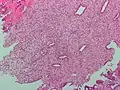

-

Endometrioid adenocarcinoma from biopsy. H&E stain. -

Micrograph of decidualized endometrium due to exogenous progesterone. H&E stain. -

Micrograph showing endometrial stromal condensation, a finding seen in menses.